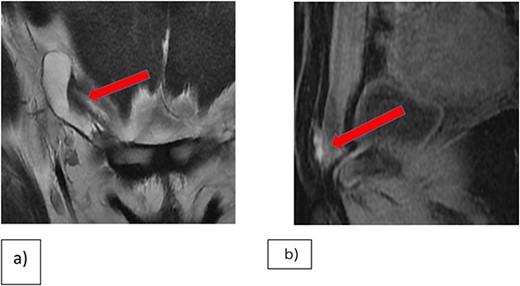

The uterus, both ovaries, and pouch of Douglas were examined. Two endometrial deposits were detected: one the anteroposterior part of the uterus and another below the base of the right fallopian tube. In addition, there was right inguinal hernial defect and a cystic lesion on the surface of the round ligament (Figs 2–4).

(a) Endometrial lesion in superoposteriar uterus. (b) Endometrial lesion in the base of right Fallopian tube.